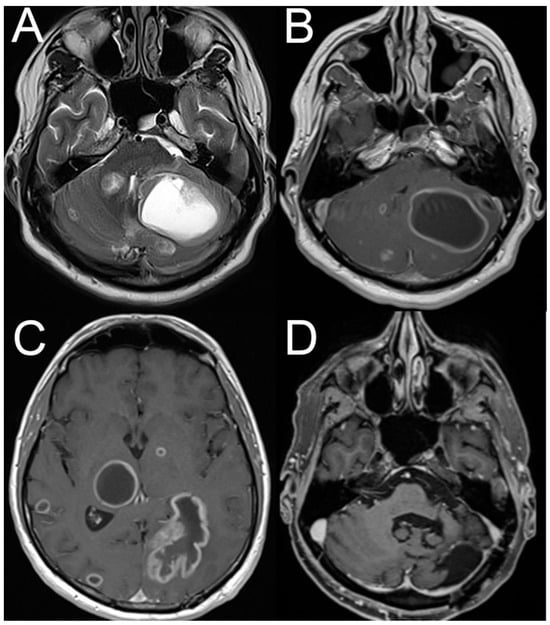

4.2. Posterior Fossa Tumors and (Other) Causes of Increased Intracranial Pressure